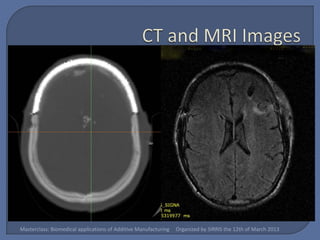

   Methods & Materials:

•    Computed Tomography (CT) scans are obtained

relevant bony structures segmented using Mimics

(Materialise NV).

 Work  closely with the surgical team

 Be very comfortable with radiographic

anatomy as well as the anatomy of the area

where you are working